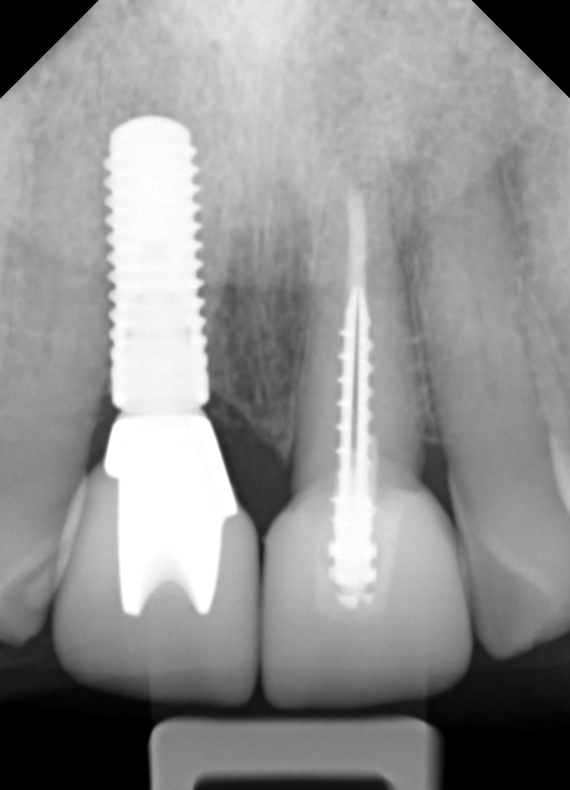

Fig 3. In a separate case, radiograph of a decayed endodontically treated tooth is shown. The decision was made to extract it before further damage to adjacent teeth and/or loss of bone could occur.

Figure 3

Fig 4. Radiograph of the implant to replace the tooth in Fig 3 (implant placed by David Levine, DDS).

Figure 4